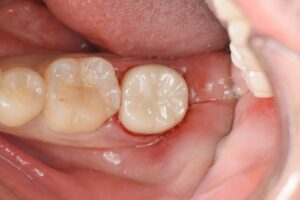

歯内療法専門医と連携して治療を行なった症例です。

虫歯と痛みが大きい部位に関しては、保険適応外の根管治療専門医が精密根管治療を行い、その後被せ物をジルコニアにて行いました。

| 精密根管治療後のジルコニアセラミック(20代女性) |

| 精密根管治療後、ジルコニアセラミックによる補綴修復を行なった。 |